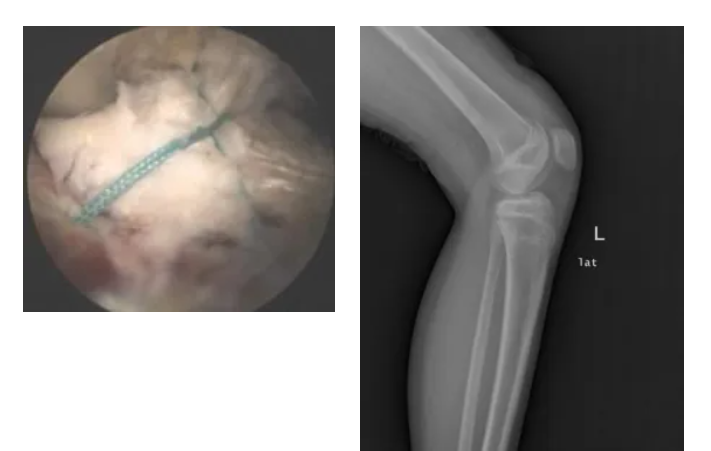

03.半月板損傷

關(guān)節(jié)鏡下微創(chuàng)行半月板成形、部分切除、盤(pán)狀半月板切除、半月板撕裂縫合等

04.髕骨脫位

關(guān)節(jié)鏡下微創(chuàng)行髕股韌帶縫合或者重建